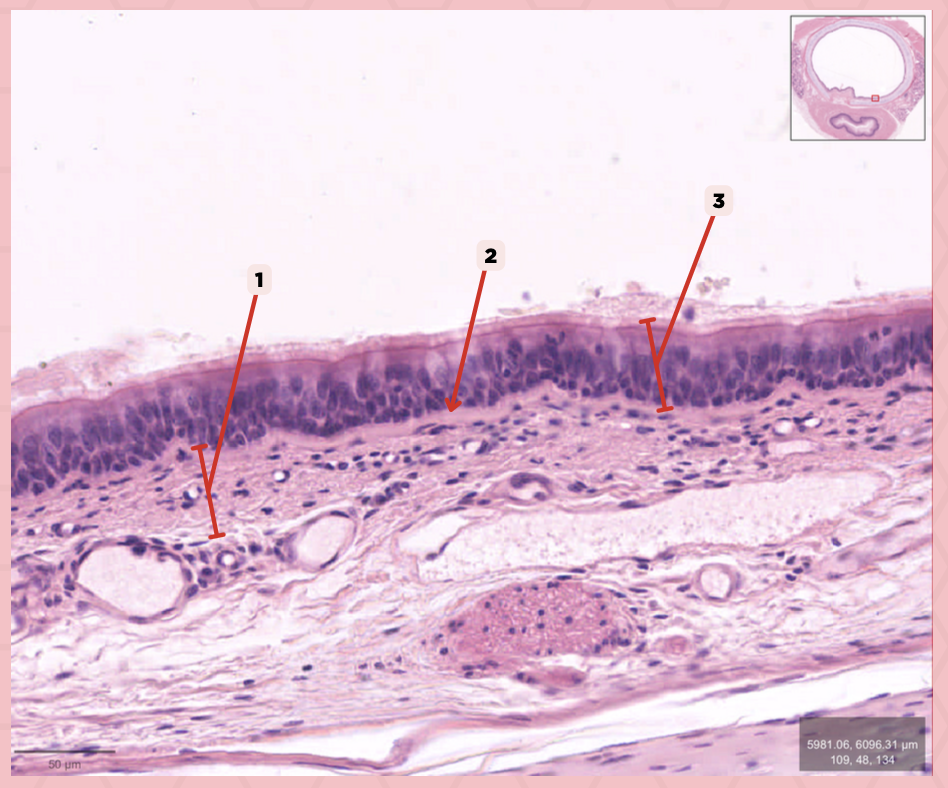

Respiratory Epithelium

Identify the structure labeled as 1.

Lamina Propria

Identify the structure labeled as 2.

Bony spicule

Identify the structure labeled as 3.